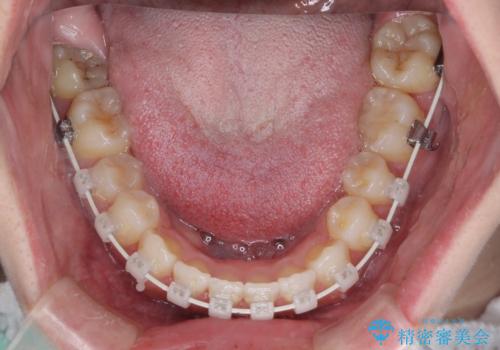

八重歯を改善 目立たないワイヤー装置での矯正治療

- 矯正装置

- 審美装置

- 八重歯を気にして来院された患者様です。

本来であれば八重歯の隣後方の歯を抜歯するのですが、その後ろの歯が乳歯であり後続永久歯もなかったため、乳歯を抜去することとしました。

前から5番目の乳歯は、後続永久歯である小臼歯と比べて幅径が大きいため、移動に時間がかかりましたが、きれいに仕上げることができました。